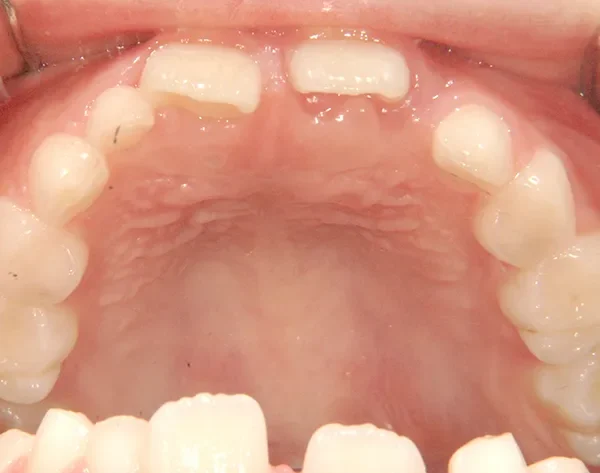

【子供の矯正(一期)】叢生・すきっ歯・永久歯が生える隙間がない・反対咬合・7歳男児【K.S様】

初診時年齢 小学校1年生 (男性) 主訴 すきっ歯・ガタガタ・受け口

診断名 叢生・反対咬合・空隙歯列 装置名

上の前歯が下の前歯より後ろに入って、受け口になっています。

下の歯は永久歯の生えるスペースがないので、オリジナル矯正装置で受け口を治して、永久歯の生えるスペースを作りました。